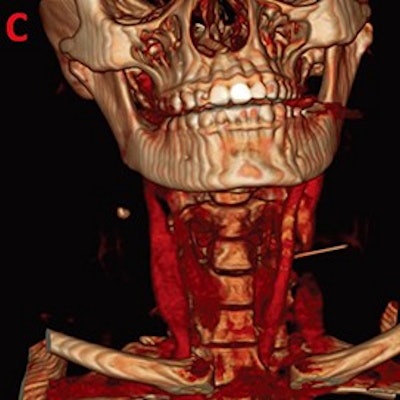

- CT confirms 3-cm swallowed dental needle in patient's neck

Radiologists don't usually interpret dental x-rays, but the novelty of this case won the interest of our readers. A 29-year-old woman in Qatar accidentally swallowed a 3-cm needle -- most likely during a dental procedure -- and CT was employed to locate it after she reported experiencing neck pain, according to a report in the April issue of Journal of Dental Anesthesia and Pain Medicine. The 3D-reconstructed images from the case are particularly striking.